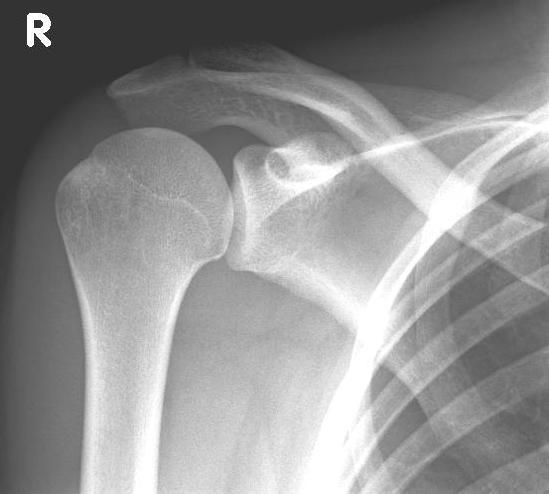

Abbildung6Conventional stem prostheses for omarthrosis and acetabular wear

left: X-ray image of a shaft prosthesis

right: anatomical shoulder prosthesis with glenoid replacement (Affinis type, Mathys company)